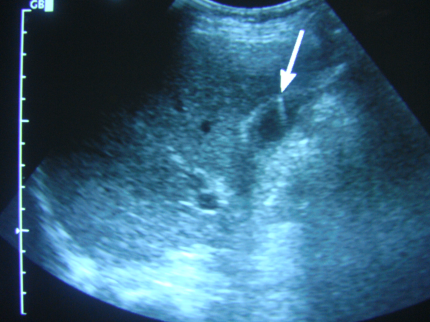

破題關鍵

這張右上腹部超音波顯示膽囊內有一個高回音病灶,並伴隨典型的「彗星尾假影」(comet-tail artifact)。這個影像特徵是診斷膽囊腺肌症(gallbladder adenomyomatosis)的重要線索,特別是當膽固醇結晶沉積在Rokitansky-Aschoff憩室時。